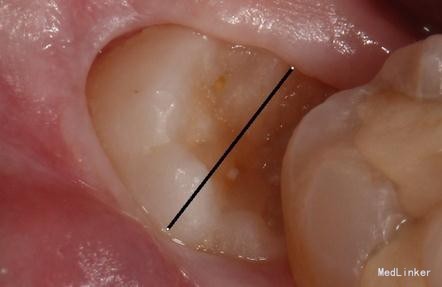

检查: 18.28颌面龋坏,质地软,牙颈部脱矿,叩诊(-),不松动。 37玻璃充填物,叩诊(-),不松动,冷热刺激正常。 38近中水平阻生,牙龈无红肿,叩诊(-),探诊有盲袋,盲袋内食物碎屑。 47缺失多年,48近中向移位,间隙1mm,叩诊(-),不松动。

治疗计划:18、28,38拔除。 37重新充填。 48观察。 治疗:28局麻下拔除。 38阻滞下拔除。